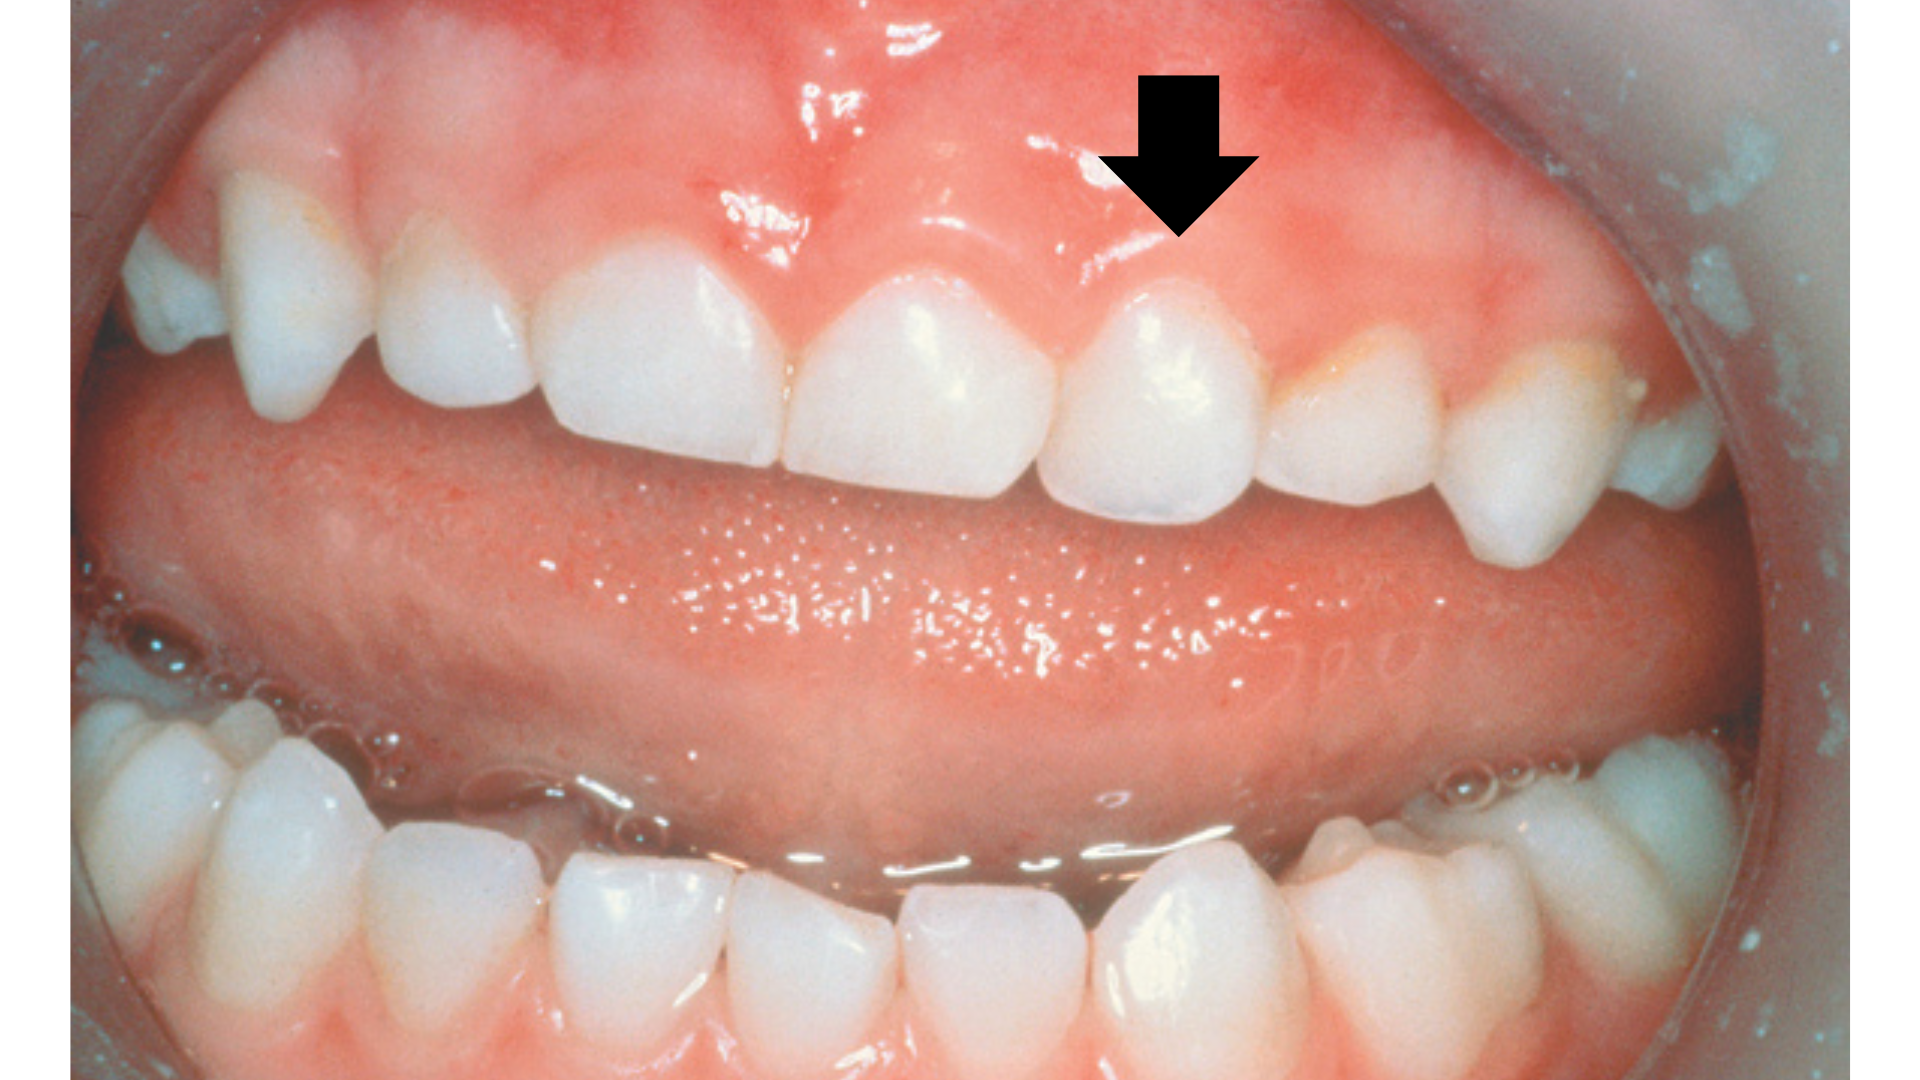

Eruption cysts

During teething, some children may develop fluid-filled sacs known as eruption cysts. These cysts are typically harmless and usually resolve as the tooth erupts through the gum. If they persist more than a couple of weeks refer to a dental professional as there are more serious but very rare conditions that present similar.

Refer to ‘Section 6.5 -Eruption Cysts' for more information